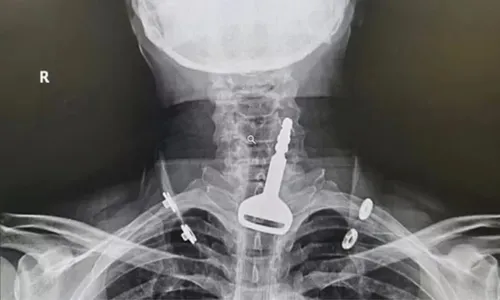

Ele foi levado às pressas a um pronto-socorro da região com quadro de asfixia e uma radiografia revelou o local exato onde a chave ficou retida.

O objeto ficou entalado nas vias respiratórias, entre a traqueia e o esôfago, provocando dificuldades em respirar.